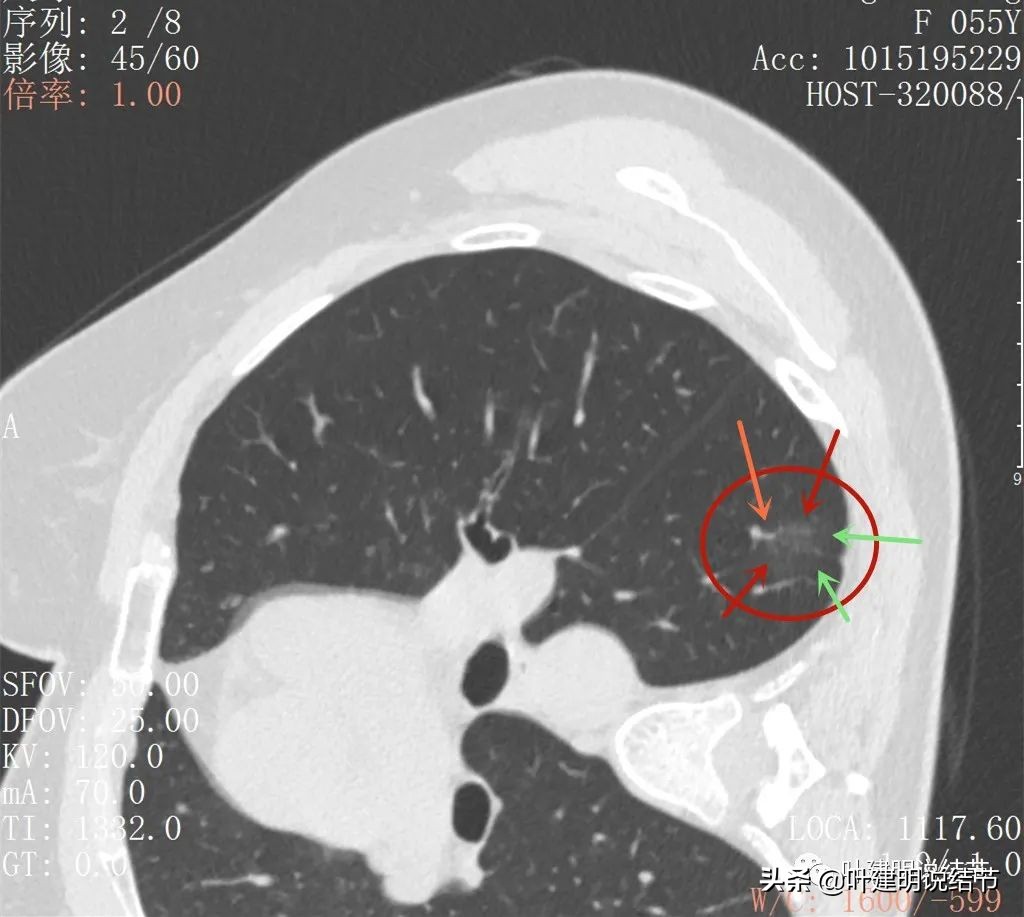

再来看2022年6月的CT图像:

小病灶轮廓清,是磨玻璃结节(红色箭头),有血管贴边或穿行(桔色箭头)

密度是磨玻璃,稍不均质,似乎略见胸膜牵拉(蓝色箭头)

整体轮廓清

病灶轮廓很清,邻近胸膜是略有影响的(蓝色箭头)